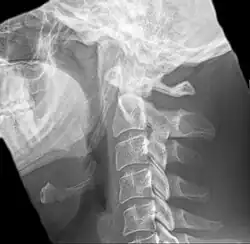

Radiograph, lateral view showing joint-like formation in ossified stylohyoid ligament -

Imaging is important and is diagnostic. Visualizing the styloid process on a CT scan with 3D reconstruction is the suggested imaging technique.[13] The enlarged styloid may be visible on an orthopantogram or a lateral soft tissue X ray of the neck.